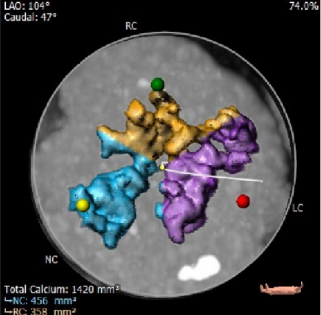

CT报告示主动脉瓣钙化明显,左右冠散在钙化斑块。

①患者主动脉根部钙化明显,瓣上钙化呈集中式分布,瓣膜植入后锚定力可,形变风险较大。

1. 主动脉瓣瓣环周长77.0mm,平均周长径24.5mm,SOV:32.6mm*351.4mm*32.2mm,瓣叶增厚,瓣上钙化明显,HU850钙化积分913mm³。

钙化评估及主动脉根部速览

这是一例有示范意义的AS患者瓣膜植入术,患者主动脉瓣根部钙化明显,呈中心聚集形态,主动脉弓部及外周血管钙化轻微,使得术者能专注于根部病变的处理。钙化的集中,为入路建立和器械过弓带来便利的同时,也对最终瓣膜的工作形态带来了很大的不确定性。所以球囊预扩在本病例中,有着很高的数据价值。一般而言,瓣上钙化很严重的情况下,存在downsize两个型号的可能。患者瓣环平均径24.6mm,术前评估downsize一个型号,推荐预装AV26瓣膜。术中经TaurusAtlas 20mm球囊预扩,钙化推移明显,适于植入AV26号瓣膜,验证了术前评估的正确性。